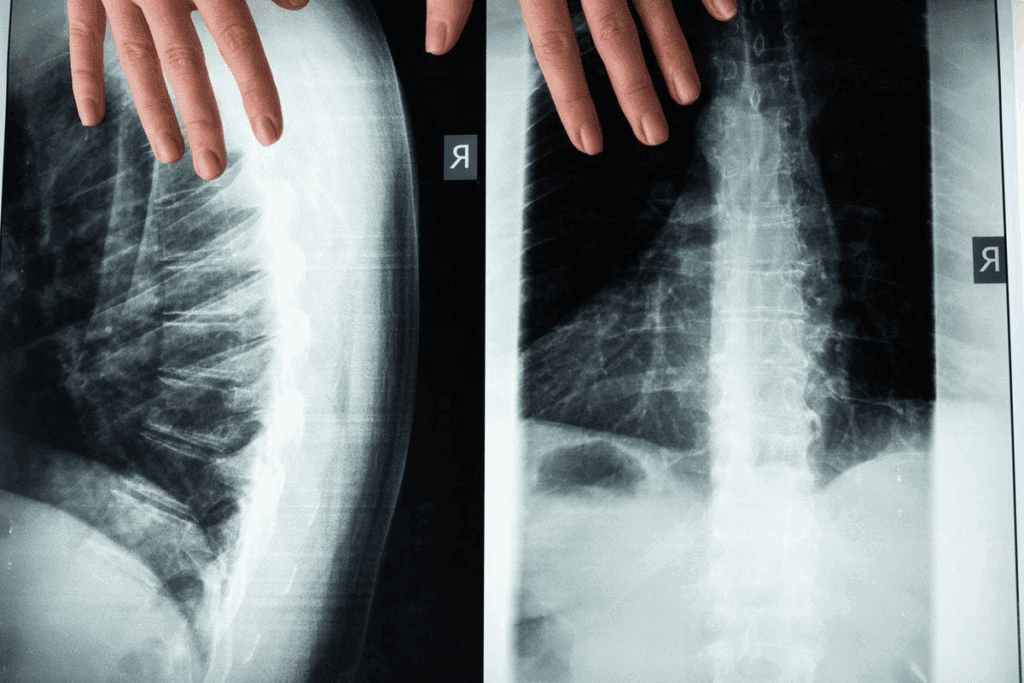

To diagnose vertebral compression fractures, we use a mix of clinical checks and advanced imaging. These steps help us spot the fracture and figure out how bad it is.

Imaging Tests and Procedures

Several imaging tests are key in spotting vertebral compression fractures. These include:

• X-rays: Give us the first look at the spine to find fractures.

• CT Scans: Show detailed images from different angles, helping us see how serious the fracture is.

• MRI: Helps us check for soft tissue damage and find other pain causes.

These tests are essential for figuring out how bad the fracture is and what treatment to use.